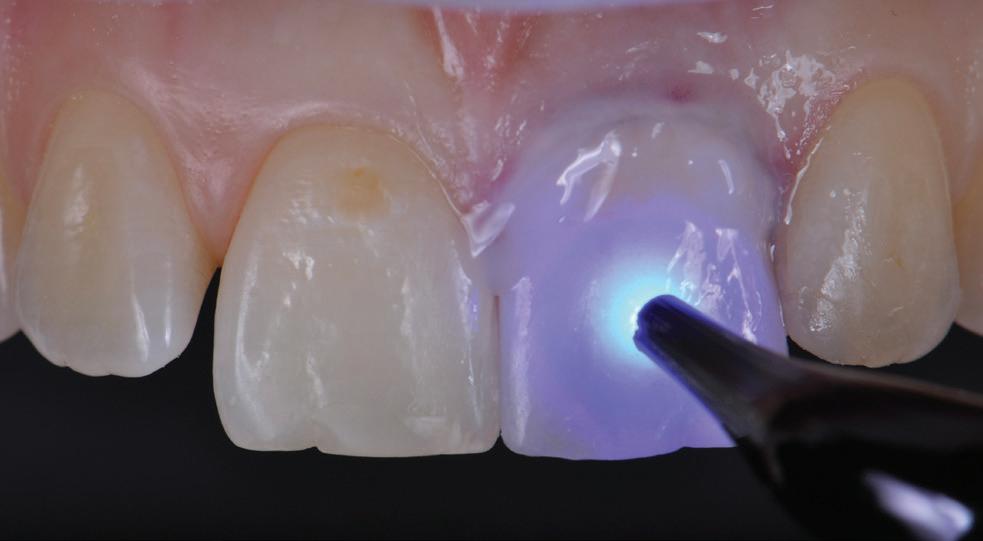

Knowing your own practice.

Often sales processes reveal that dentists have not understood their strengths and weaknesses and expose themselves to shocks during the selling process. Most accountants simply churn out tax returns for a variety of small businesses and individuals with no idea regarding how a dental practice compares with key benchmarks. These accountants are inadequate in representing their dental clients if a sale process reveals weakness whereas their client had assumed that they would have been advised by their accountant of issues that they should have addressed long before listing for sale.

Practice managers negative impact on profit and sale price.

Unfortunately, most practice managers —other than courtesy titles given to experienced receptionists—are profit destroyers rather than profit enhancers.

“Innocent” asked for a practice valuation and was shocked at the low figure. He sought deeper analysis and I pointed out that his non-clinical staff cost as a percentage of practice fees was extraordinarily high. With superannuation and work cover insurance, the “manager” was costing his practice $110,000 per year—and this was quite a few years back. The remainder of the non-clinical staff together cost as much as the average of all dental practices. The manager was not saving on other staff and her cost effectively reduced the capital value of his practice by around $400,000. He took a deep look at what the manager actually did and found out that with the assistance of a visiting bookkeeper and a bit of tightening of dental patient appointments and chairside assistants’ hours, he could dispense with the manager, reducing non-clinical staff overhead by $110,000. The practice manager’s position had long been redundant. A couple of years later he was able to sell his significantly more profitable practice for its true value.

Preparing to buy a dental practice.

The first thing to understand is that the vast majority of accountants and financial advisers know “diddly squat” about the differences between good and mediocre dental practices.

If they do have one or two dental clients, their interaction is invariably limited to completing annual tax and financial returns, but they are clueless as to how their clients’ practices compare with wellperformed practices or what to advise a buyer to look for beyond averaging the last three years’ profits.

Accountants’ advice seriously lacking

While many accountants have signage proclaiming that they give “business advice”, most do tax returns and confine advice to tax issues.

There is no point in comparing a dental client with a plumbing contractor or an Australia Post and lottery agent. Wisdom does not appear to improve with size of accounting practices. I have seen accountants from top-end-of-town accounting groups badly let down dentists with misinformed advice.